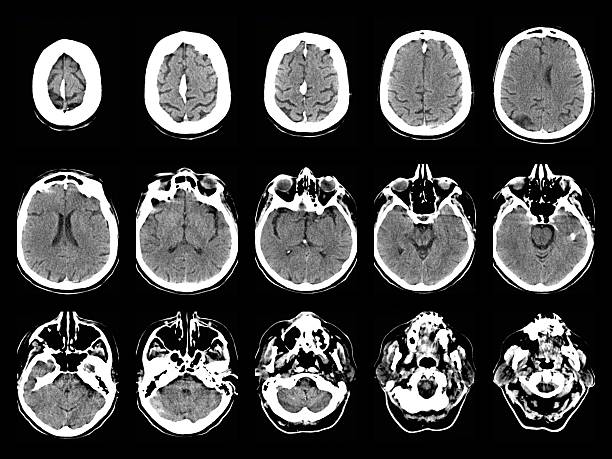

老年神經(jīng)系統(tǒng)會出現(xiàn)哪些問題?

老年神經(jīng)系統(tǒng)疾病給全球醫(yī)療保健系統(tǒng)帶來了沉重的負(fù)擔(dān)。閱讀文章了解更多信息。

世界人口正在老齡化,老年人的數(shù)量正在增加。隨著預(yù)期壽命的延長,老年人患神經(jīng)系統(tǒng)疾病的幾率也在上升。了解和解決這些問題對于為老齡人口提供適當(dāng)?shù)尼t(yī)療保健和支持至關(guān)重要。老年神經(jīng)系統(tǒng)疾病給全球醫(yī)療保健系統(tǒng)帶來了沉重的負(fù)擔(dān)。這些疾病通常需要長期護理、專業(yè)醫(yī)療服務(wù)和持續(xù)管理。通過有效解決和治療神經(jīng)系統(tǒng)問題,可以優(yōu)化醫(yī)療保健資源以滿足老年人的需求。

神經(jīng)系統(tǒng)疾病,也稱為神經(jīng)系統(tǒng)疾病或病癥,是影響中樞神經(jīng)系統(tǒng)(大腦和脊髓)、周圍神經(jīng)系統(tǒng)(大腦和脊髓以外的神經(jīng))或兩者的疾病。這些疾病是由神經(jīng)系統(tǒng)的結(jié)構(gòu)、功能或化學(xué)異?;蚬δ苷系K引起的。